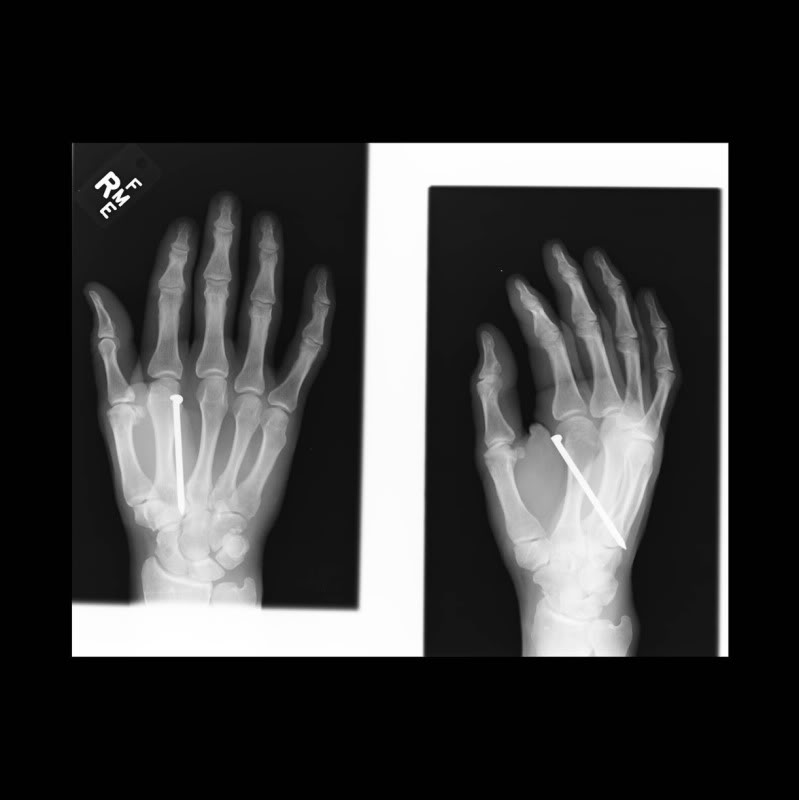

I like that dually.View attachment 184305 View attachment 184306 Picked up these two crème puffs yesterday.